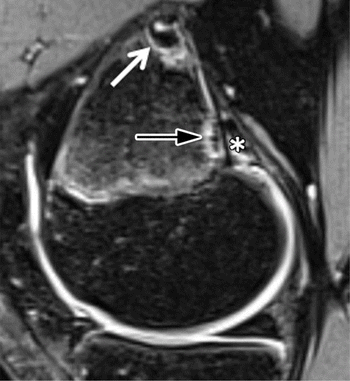

MRI-detected bony lesions located right above the knee in young athletes are common and harmless – and they should not be confused with more serious conditions, new research has revealed.